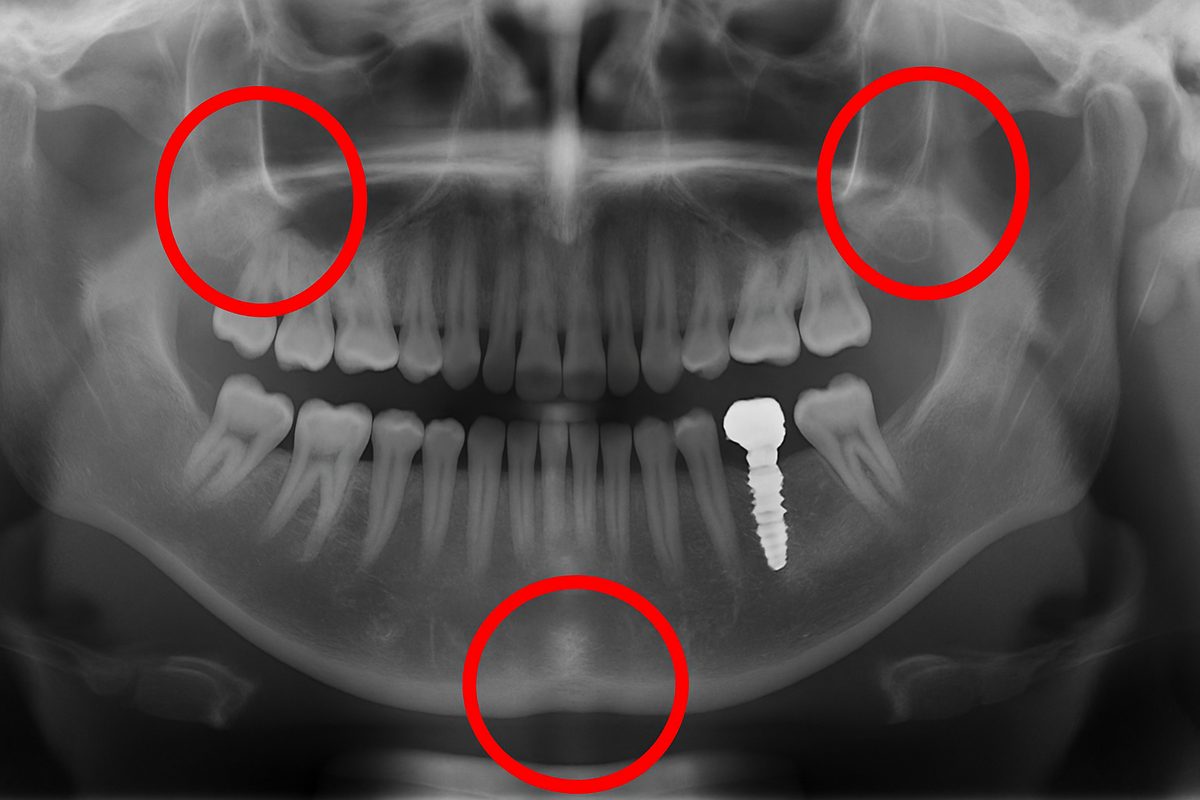

Peri-implantitis is an infection that affects the gum and bone around an implant. Look for redness, swelling, bleeding when brushing, a bad taste or persistent bad breath, and possible pus. Left untreated, infection can erode bone and threaten the implant.

A mobile implant or one that feels loose is a major warning sign. Early failure usually comes from poor osseointegration (the implant didn’t bond to bone). Late failure can come from overload, untreated infection, or bone loss. If you can move the crown or feel wobble, see your dentist quickly.

Gum Recession and Bone Loss

Gum recession around an implant exposes metal or the edge of the crown and can affect appearance. Bone can shrink over time from infection, poor loading, or lack of maintenance. This can make the implant look longer and reduce support.